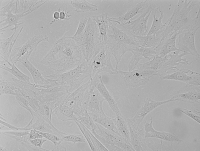

细胞形态 |

内皮细胞样 |

人视网膜微血管内皮细胞采用胶原酶-中性蛋白酶混合消化法结合密度梯度离心法、后通过内皮细胞专用培养基培养筛选制备而来,人视网膜微血管内皮细胞分离自视网膜组织;视网膜居于眼球壁的内层,是一层透明的薄膜。视网膜由色素上皮层和视网膜感觉层组成,两层间在病理情况下可分开,称为视网膜脱离。色素上皮层与脉络膜紧密相连,由色素上皮细胞组成,它们具有支持和营养光感受器细胞、遮光、散热以及再生和修复等作用。组织学上视网膜分为10层,由外向内分别为:色素上皮层、视锥、视杆细胞层、外界膜、外颗粒层、外丛状层、内颗粒层、内丛状层、神经节细胞层、神经纤维层、内界膜。视网膜内层为衬于血管膜内面的一层薄膜,有感光作用;后部鼻侧有一视神经乳头。视网膜上的感觉层是由三个神经元组成。第一神经元是视细胞层,专司感光,它包括锥细胞和杆细胞。视杆细胞主要在离中心凹较远的视网膜上,而视锥细胞则在中心凹处多。第二层叫双节细胞,约有10到数百个视细胞通过双节细胞与一个神经节细胞相联系,负责联络作用。第三层叫节细胞层,专管传导。视网膜是一层菲薄的但又非常复杂的结构,它贴于眼球的后壁部,传递来自视网膜感受器冲动的神经纤维跨越视网膜表面,经由视神经到达出口。视网膜的分辨力是不均匀的,在黄斑区,其分辨能力强。它是组成血管腔面单层扁平上皮样细胞,它所产生和分泌的生物活性物质对维持血管张力、调节血压、抗血栓形成等有重要作用,在视网膜血管疾病的发病机制中有重要病理生理学意义。由于从不同的组织和器官获得的内皮细胞具有不同的特性,在脑和视网膜中,这些内皮细胞具有内屏障的功能,在调节血管生理状态,释放血管活性物质以及新生血管的形成中发挥着重要作用,体外分离培养RCEC对研究视网膜血管性疾病发生发展的病理生理机制以及疾病的早期防治具有重要临床意义。视网膜血管的生成是由内皮细胞、外膜细胞、星形胶质细胞产生的各种正负调节因子产生平衡而成。大部分致盲性疾病如糖尿病视网膜病、早产儿视网膜等都与血管生成有关。人视网膜微血管内皮细胞病变的主要生理变化有视网膜炎症、视网膜动脉硬化以及视网膜出血。 |